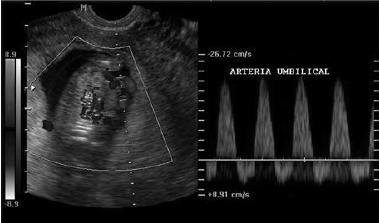

Considere a imagem a seguir:

Assinale a alternativa que indica corretamente o que a imagem representa e seu possível significado.